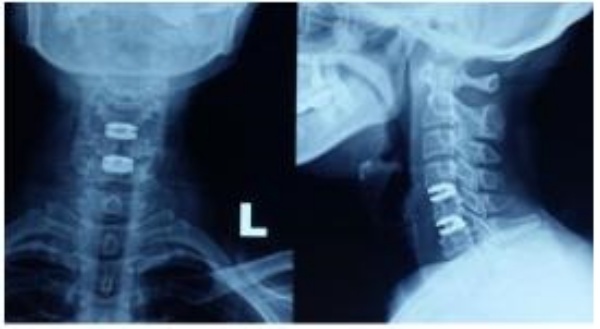

Thời gian khám lại trung bình là 37.66 ± 9.28 tháng. 100% bệnh nhân đạt tỷ lệ hồi phục hội chứng tủy cổ tốt và rất tốt. VAS sau khám lại trung bình 1.29 ± 1.69, JOA trung bình 16.13 ± 2.79 điểm, NDI trung bình 7.32 ± 13.63 %, tỷ lệ hồi phục (RR) 87.29 ± 17.90 %. Trên phim Xquang 100% bệnh nhân trên không mất vững cột sống cổ, đĩa đệm nhân tạo đều ở vị trí tốt, không di lệch hay trượt thứ phát, không phát hiện trường hợp nào lún đĩa đệm. Những bệnh nhân sau mổ 6 tháng ROM góc cúi trung bình 27.79 ± 7.940 (trước mổ 17.76 ± 8.220, n = 38), ROM góc ngửa trung bình 45.63 ± 13.280 ( trước mổ 28.55 ± 11.140, n = 38). 3/48 vị trí thay đĩa đệm nhân tạo quá phát xương ở độ I (6.25%), 45/48 vị trí thay đĩa đệm bình thường độ 0 (93.75%) (n=48), tỷ lệ quá phát xương tại vị trí thay đĩa đệm 1.99%/ năm. Tỷ lệ thoái hóa đĩa đệm liền kề là 0.85%/ năm. Mức độ hài lòng của bệnh nhân đạt 97.37%.

Trước mổ 38 bệnh nhân được khám lại sau 6 tháng, (ROM) đo được góc cúi 17.760 ± 8.220, góc ngửa 28.55 ± 11.140. Sau mổ vào thời điểm kiểm tra lại đo được góc cúi 27.790 ± 7.940, góc ngửa 45.63 ± 13.280. Như vậy, sau phẫu thuật chỉ số ROM đã được cải thiện một cách đáng kể, sự khác biệt này có ý nghĩa thống kê với p < 0.05. Sau khi phẫu thuật các mỏ xương đã được lấy đi, đĩa đệm thoái hóa, nhân nhầy thoát vị cũng được lấy đi, tái tạo chiều cao khoảng gian đốt sống, và tiến hành thay đĩa đệm nhân tạo có khớp. Như vậy, bên cạnh đạt được sự giải phóng chèn ép thần kinh, tái tạo chiều cao khoảng gian thân đốt sống như các phẫu thuật ACDF thì thay đĩa đệm nhân tạo có khớp còn ưu thế hơn hẳn ở duy trì và cải thiện tầm vận động CSC.